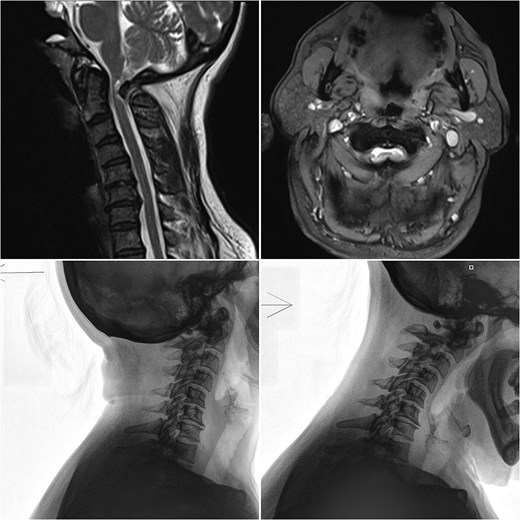

A 46-year-old female presented with gait instability and decreased sensation in her limbs. Clinical examination revealed an ataxic gait, hyperreflexia, and left-sided hemispasticity. Magnetic resonance imaging (MRI) of the cervical spine showed C1-C2 arthrosis and anterior C1 subluxation (Fig. 1), causing central canal narrowing and myelopathy. Surgical treatment was planned, including C1 laminectomy, and C1-C2 posterior fixation with fusion. A preoperative CT vertebral angiography was performed.

Sagittal and axial MRI, along with flexion/extension X-rays of the cervical spine, demonstrating anterior C1 subluxation, central canal narrowing, and myelopathy.